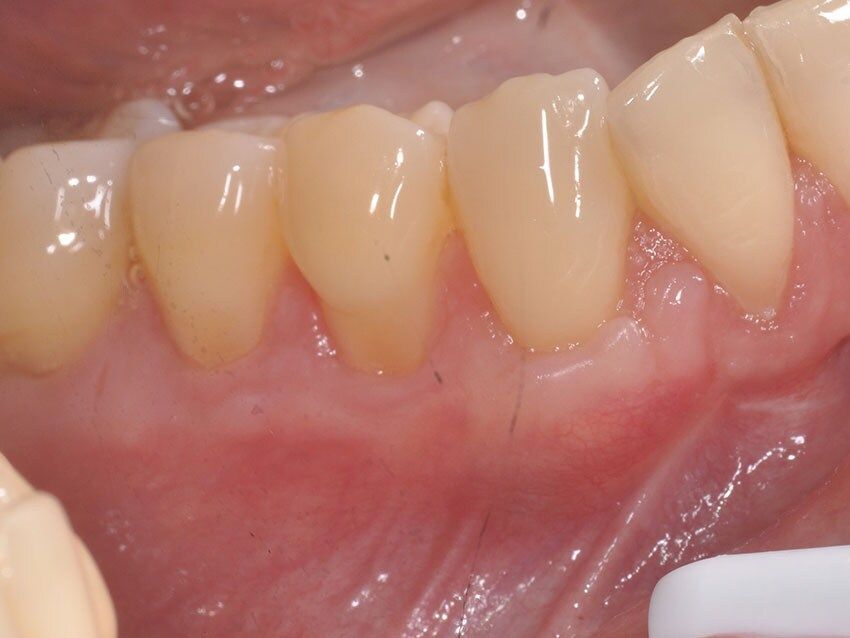

La chirurgia muco gengivale include i trattamenti dedicati alla correzione di recessioni, difetti gengivali e alterazioni estetiche del sorriso. Richiedono una tecnica che funziona nelle mani di pochi, per questo il nostro centro si avvale di uno specialista di fama internazionale, per risultati naturali, che garantiscano il successo atteso e, soprattutto, siano stabili nel tempo.

Tutti gli interventi di chirurgia orale vengono eseguiti in una sala chirurgica dedicata, in presenza di un medico anestesista, con possibilità di ricorrere alla sedazione cosciente, una procedura anestesiologica sicura e controllata che permette al paziente di entrare in uno stato di profondo rilassamento, pur rimanendo sveglio e collaborante, riducendo ansia e stress e garantendo serenità e comfort al paziente durante tutta la procedura.